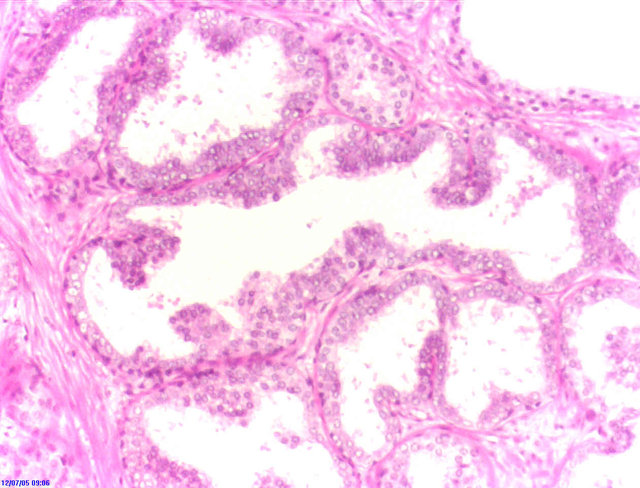

©wikipedia.org/KGH, CC BY-SA 3.0

© wikipedia.org/Alex brollo, CC BY-SA 4.0

© wikipedia.org/Alex brollo, CC BY-SA 3.0